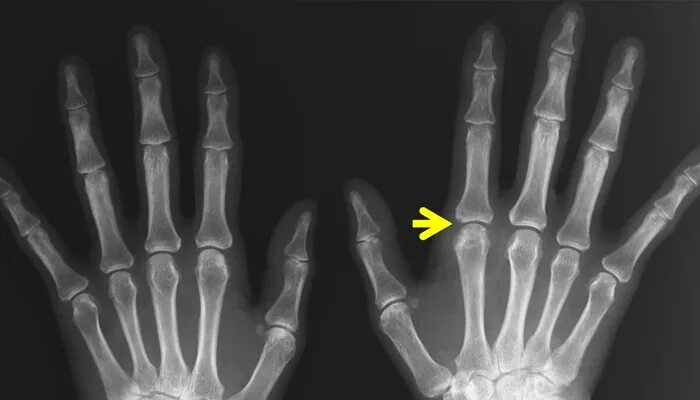

Артроз разница